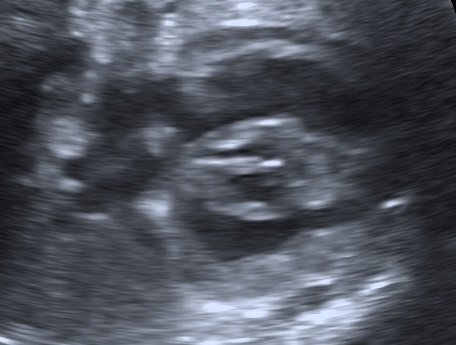

The gestational week does not influence the diagnosis of polyhydramnios. The size of the uterus could be suggesting of this condition, however the diagnosis should be made during ultrasound examination. There are two common ways to estimate the volume of the amniotic fluid:

- Single Deepest Pocket (SDP). A vertical measurement in the deepest amniotic fluid pocket. Values below 2 cm indicate oligohydramnios, values over 8 cm indicate polyhydramnios (8-11: mild, 12-15: moderate, > 16: severe). In multiple gestation, a range of 3–8 cm is defined as normal. Another technique is the

- Amniotic Fluid Index (AFI). This is the sum of vertical measurements of all four quadrants (polyhydramnios usually >24).